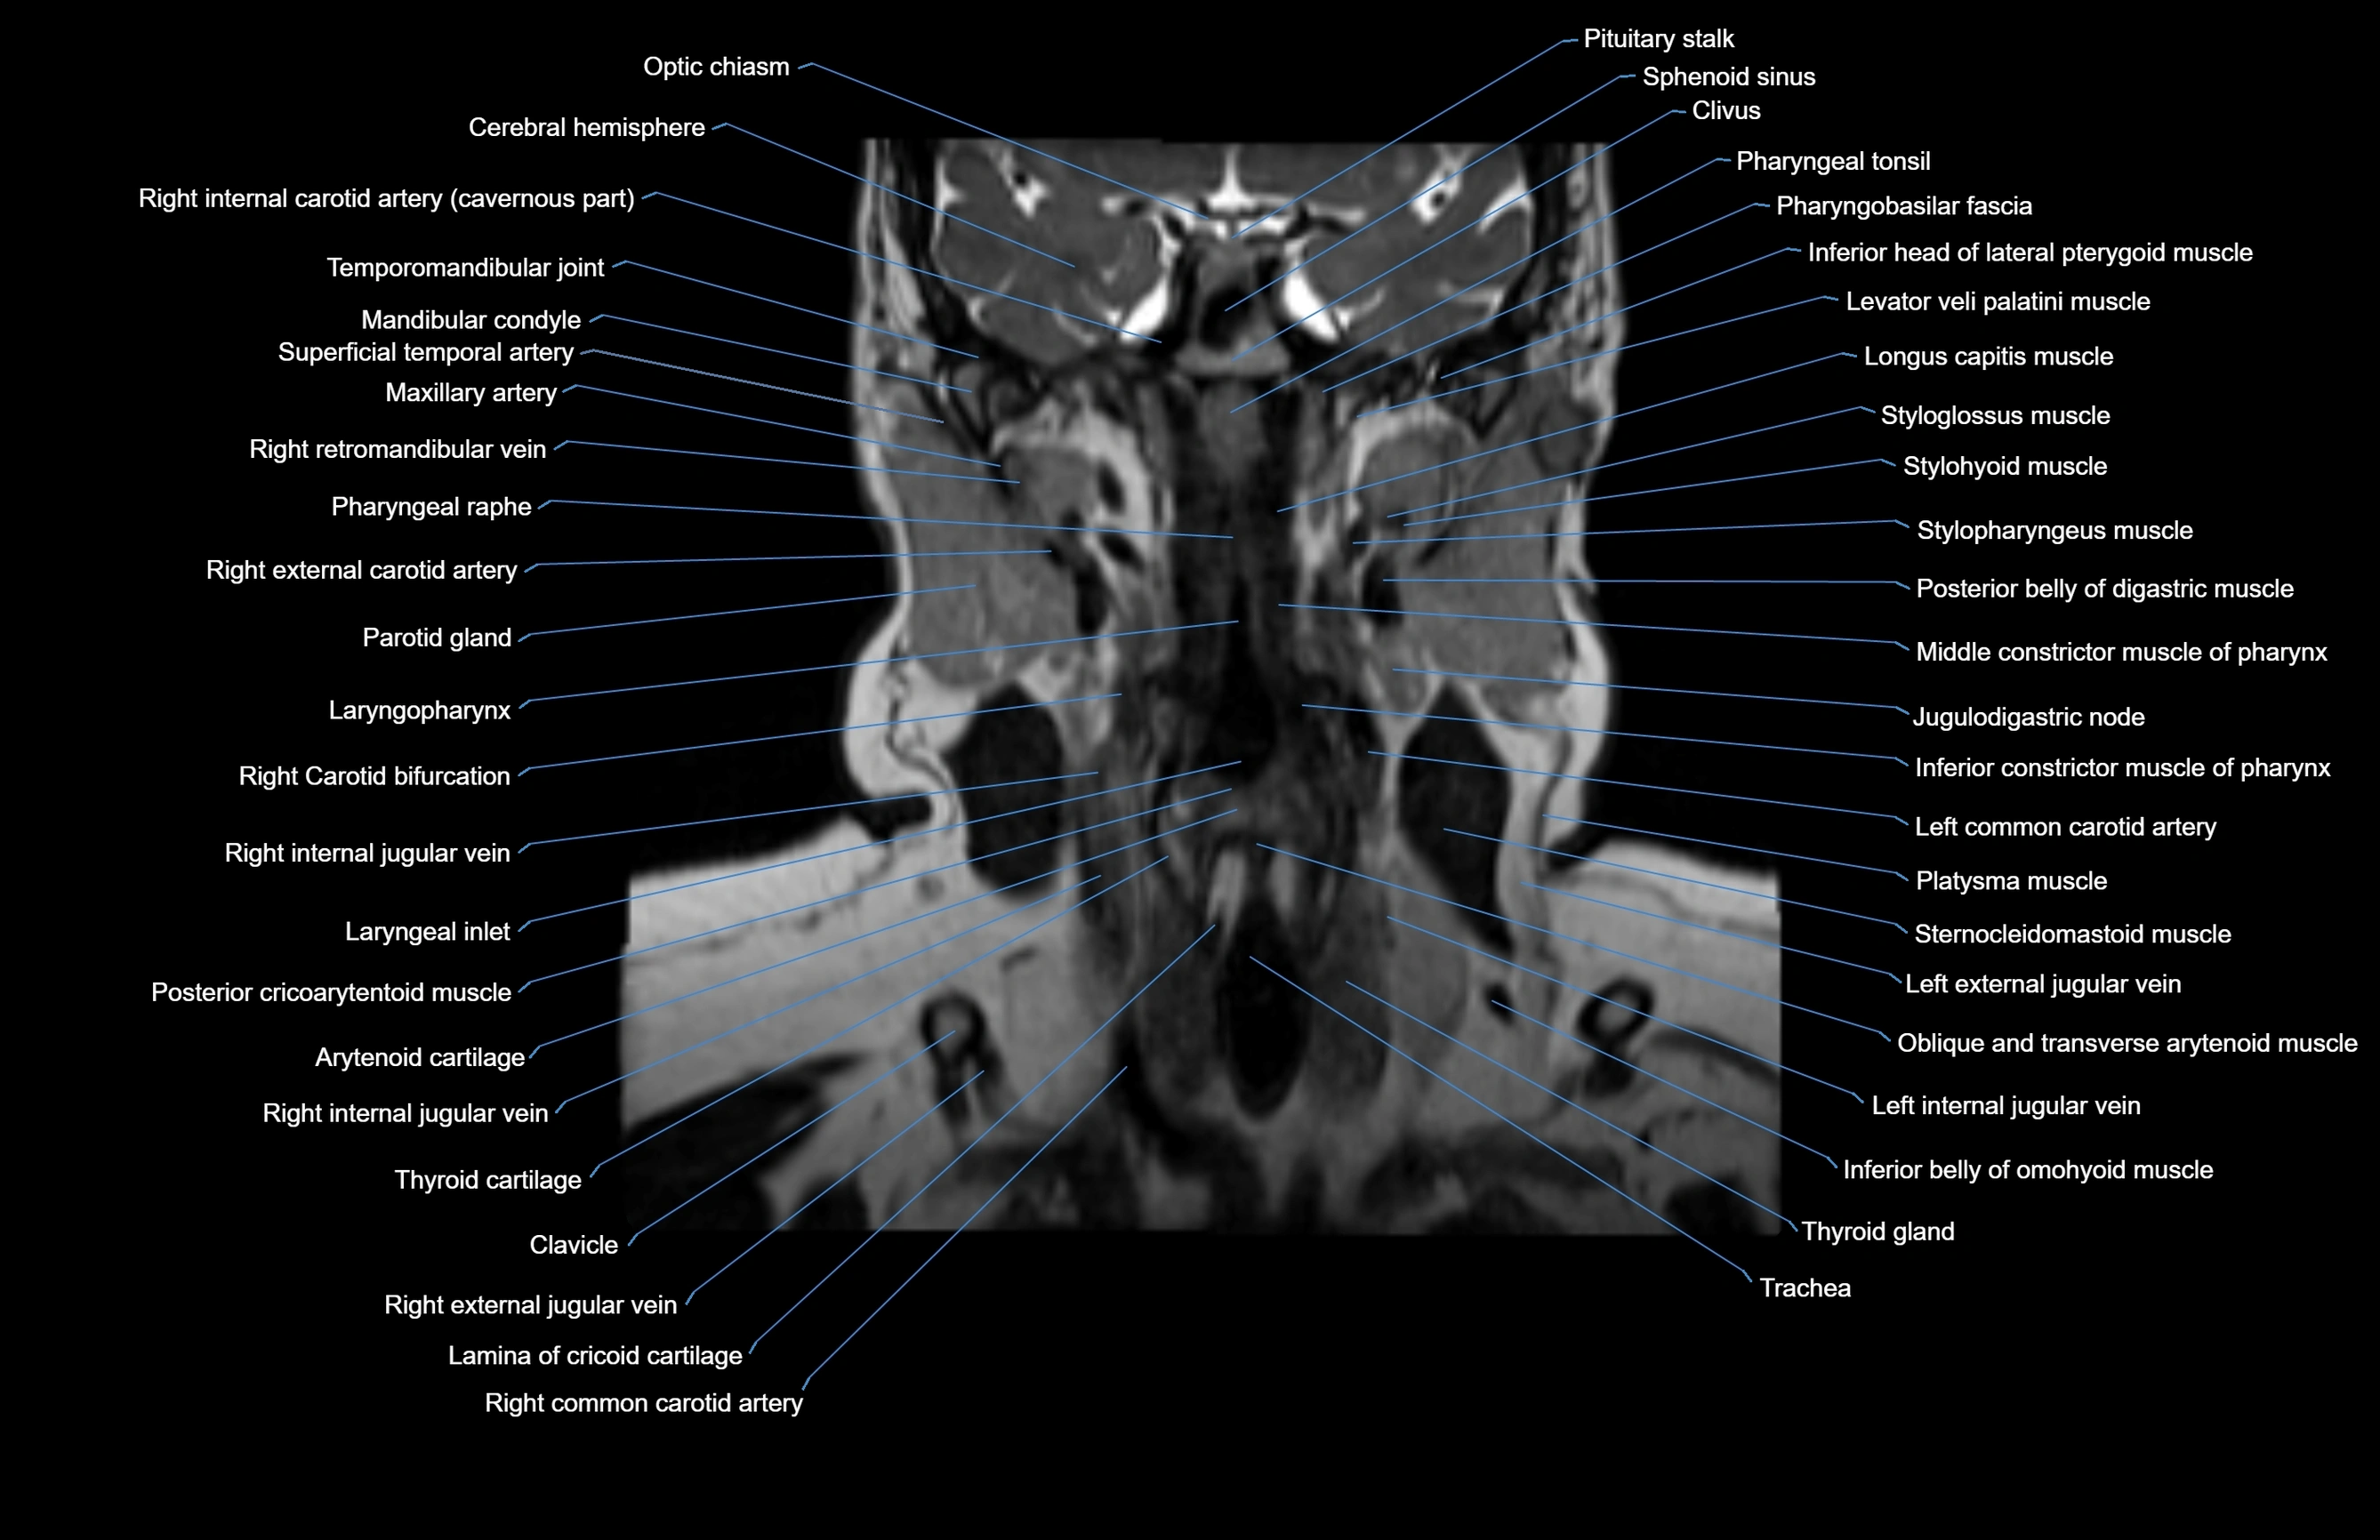

MRI images